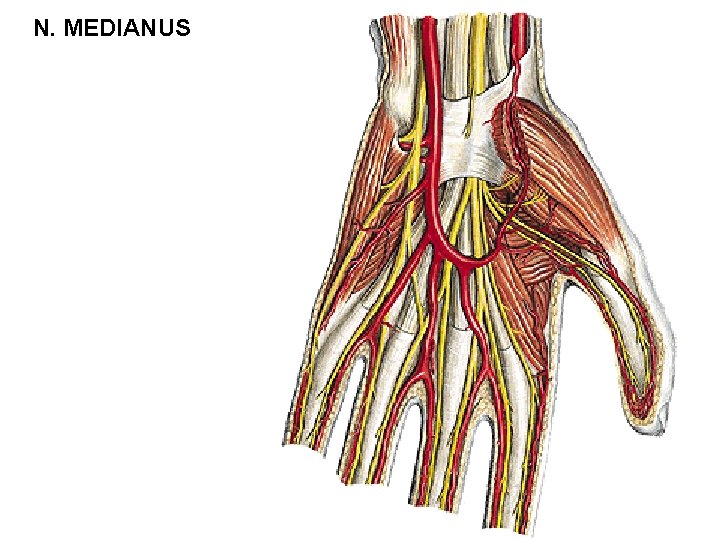

N. MEDIANUS - r. thenaris - m. abductor pollicis brevis - m. flexor pollicis brevis – caput superficiale - m. opponens pollicis - nn. digitales palmares communes - mm. lumbricales (I, II) - nn. digitales palmares proprii - r. communicans cum nervo ulnari